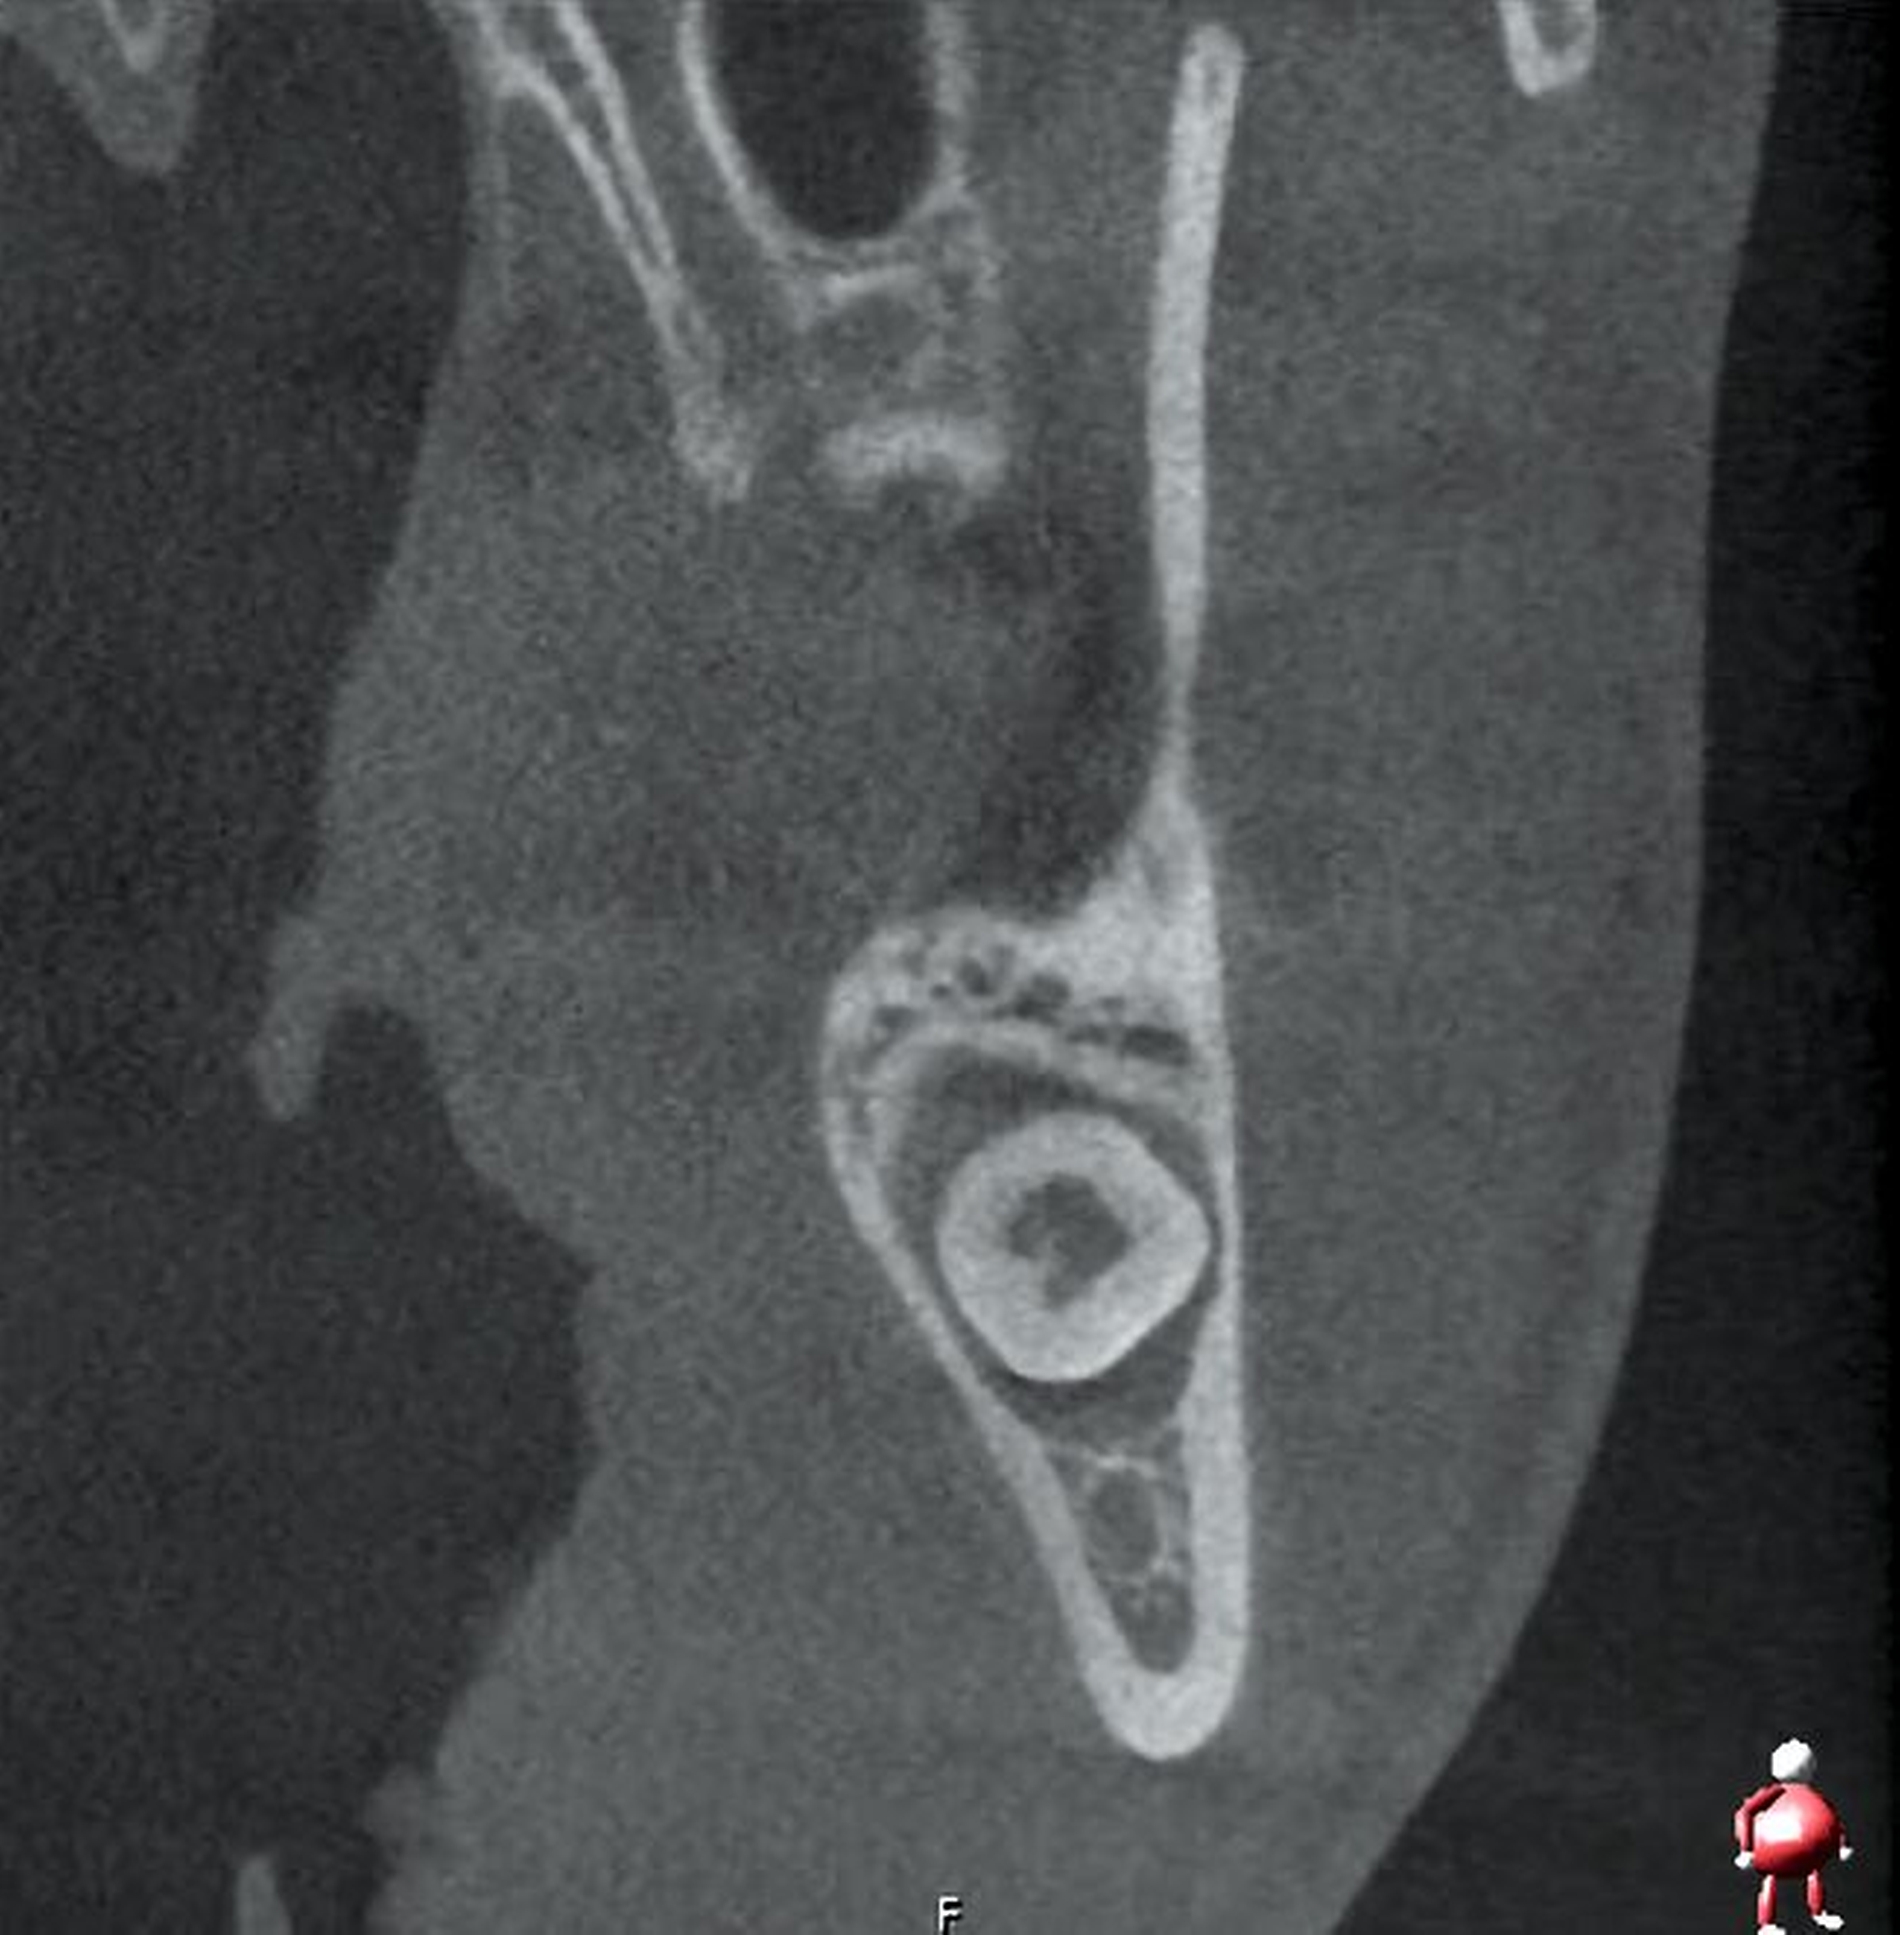

Im Oberkiefer zeigte sich auf der linken Seite neben dem hoch verlagerten und retinierten Zahn 28 ein ebenfalls hoch verlagerter und retinierter Zahn 29 (Abbildung 4) mit enger Lagebeziehung zur Kieferhöhle. Im rechten Oberkiefer erkennt man neben dem hoch verlagerten und retinierten Zahn 18 eine Doppelanlage des Zahnes 19 ebenso in enger Lagebeziehung zur Kieferhöhle (Abbildung 5).